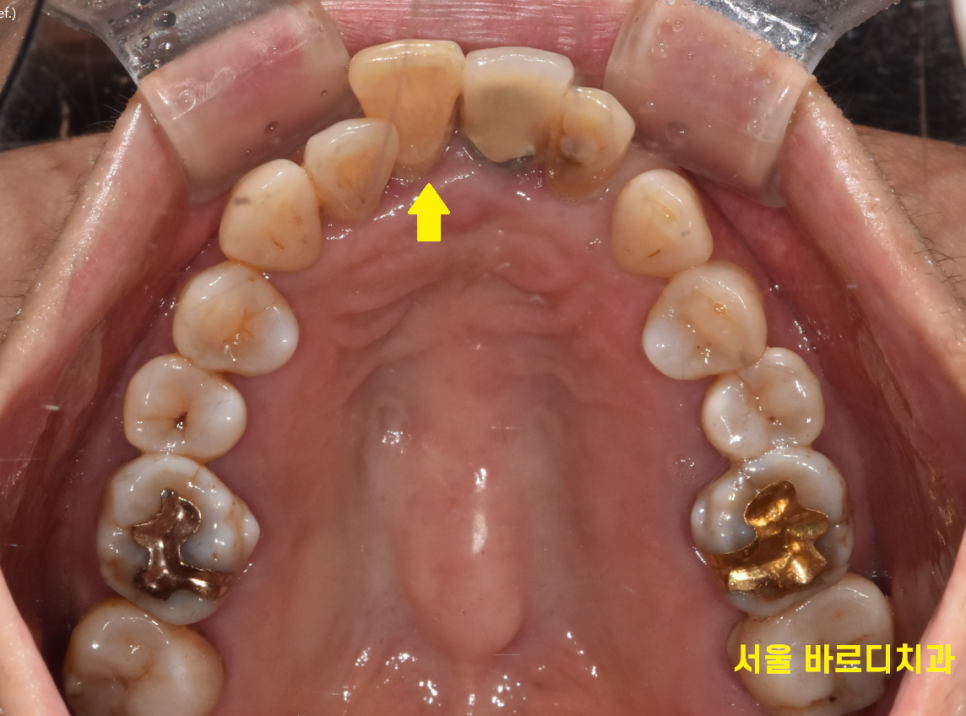

231107

오늘 치료의 핵심은 자연스럽게 회복하자! 였습니다.

뽑고 임플란트를 해야하는 치아 사이로

이미 예전에 해둔 임플란트 치아가 있었습니다.

가운데 낀 형태죠.

새로 하는 임플란트 보철과

기존 보철을 자연스럽게 연결해주어야합니다.

나중에 만든 티가 나지 않도록

이건 보철 할 때 신경 쓰도록 하고

우선 윗니 앞니 흔들림으로 내원하신게

잇몸 뼈가 없었기 때문에

임플란트 시술 시 잇몸 뼈를 두둑하게 채워넣었습니다.

앞니의 경우 잇몸 볼륨이 빵빵해야

나중에 보철을 해도 예쁘거든요~

잇몸 뼈가 푹 꺼져 보이면 나이가 들어 보일 수 있고

보기 싫어집니다.